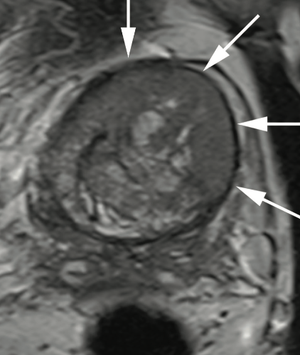

Dr. Judd W. Moul, MD, and colleagues present the case of a man, aged 73 years, with a prostate-specific antigen level of 110 ng/mL after 4 negative prostate biopsies and 4 negative prostate MRIs.